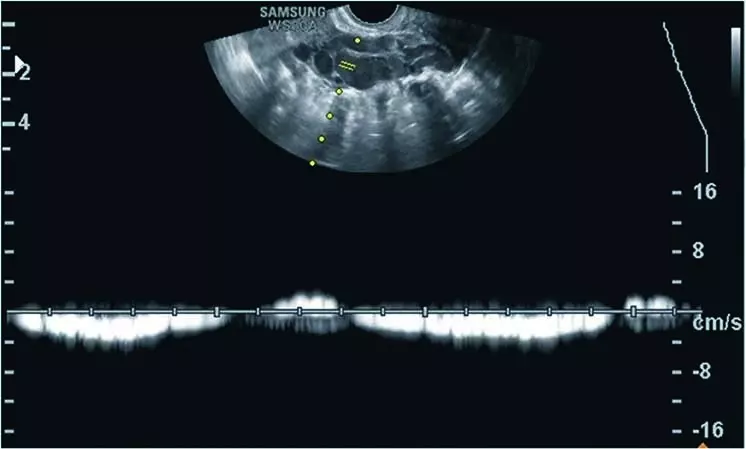

Po ok. 3 miesiącach występowania dolegliwości pacjentka zgłosiła się do lekarza rodzinnego, który po wykonaniu badań podstawowych [morfologia, CRP (ang. C reactive protein), parametry życiowe – wszystkie w normie], ze względu na opisywany związek dolegliwości z cyklem miesiączkowym i współżyciem zalecił konsultację ginekologiczną. W badaniu dwuręcznym stwierdzono niewielką tkliwość przydatków i macicy, we wziernikach obecność obfitej, niezapalnej wydzieliny w pochwie, pH 4.0. Lekarz ginekolog wykonał również ultrasonograficzne (USG) badanie przezpochwowe, nie stwierdzając nieprawidłowości. Podejrzewając zapalenie przydatków, zalecił antybiotykoterapię i dalsze konsultacje w przypadku braku poprawy. Antybiotykoterapia nie zmniejszyła dolegliwości bólowych, pacjentka była również konsultowana przez chirurgów i gastrologów, wykonano USG jamy brzusznej oraz komplet badań biochemicznych, nie zdiagnozowano przyczyny bólu. W czasie procesu diagnostycznego podejmowano próby leczenia empirycznego za pomocą doustnej antykoncepcji hormonalnej, leków rozkurczowych, niesterydowych leków przeciwzapalnych i antybiotyków – bez pozytywnego efektu. W trakcie kolejnej konsultacji ginekologicznej, ze względu na podejrzenie endometriozy, pacjentce zaproponowano laparoskopię diagnostyczną, w trakcie której nie stwierdzono nieprawidłowości. Wobec niestwierdzenia patologii mogącej tłumaczyć objawy poinformowano pacjentkę o możliwości rozważenia histerektomii z przydatkami bądź próby rozważenia zaakceptowania dolegliwości. Ostatecznie, po ok. 1,5 roku od wystąpienia pierwszych objawów, pacjentka trafiła na konsultację do III Kliniki Ginekologii. W trakcie ponownego przezpochwowego badania USG uwagę zwróciły następujące znaleziska: liczne poszerzone naczynia żylne w obrębie myometrium (ryc. 1) oraz poszerzone naczynie żylne w okolicy lewych przydatków – żyła jajnikowa lewa (ryc. 2). Po uciśnięciu sondą pacjentka podawała jedynie nieznaczne dolegliwości w okolicy lewego jajnika, natomiast bardzo żywo reagowała bólowo przy ucisku okolicy poszerzonego naczynia. W badaniu dopplerowskim w poszerzonej żyle jajnikowej stwierdzono nieprawidłowy, wahadłowy przepływ (ryc. 3). Na podstawie obrazu USG wysunięto podejrzenie zespołu PCS. W kolejnym etapie diagnostyki wykonano badanie rezonansu magnetycznego z opcją naczyniową, w którym stwierdzono znaczne poszerzenie splotów żylnych przymacicz oraz żyły jajnikowej lewej, potwierdzając rozpoznanie PCS.

Ryc. 3. W przezpochwowym badaniu USG w opcji dopplera pulsacyjnego stwierdzono wahadłowy przepływ w obrębie poszerzonej żyły jajnikowej